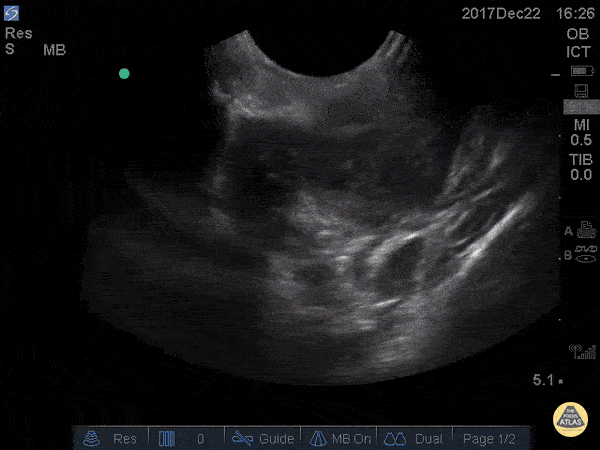

Soft Tissue - Peritonsillar Abscess

This is an example of a peritonsillar abscess as seen with a high-frequency endocavitary probe. About 3ml of pus was drained with significant relief. Notice that just deep to the abscess is big red. It's not always lateral! Dr. Jason Tanguay